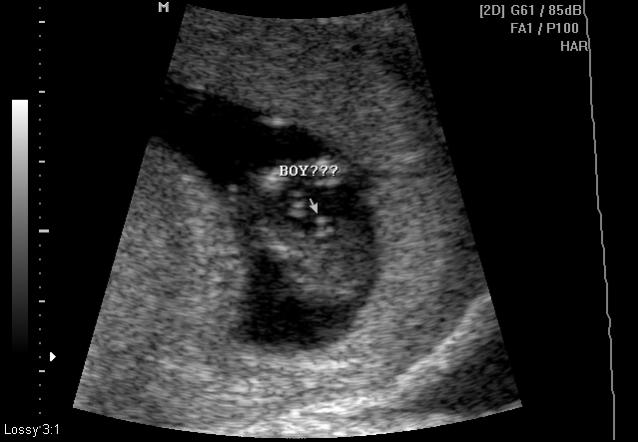

Aqua's Bubs Nub for my GenderDreaming friends

UPDATE - ITS a BOY! from the 17th week ultrasound . Thank you all.. Just feels great

I had my U/S on Friday. We did not expect the Peri to take a guess on our gender but to our surprise she did. She also did a butt shot which I thought was too early for 12.2 weeks. I request you ladies to take a look and let me know your opinion and please let me know which one among the 2 pictures is more accurate in determining. Thanks for looking.

The scratched out part on the butt shot is the perinatologist's guess.

Attachment 125Attachment 127